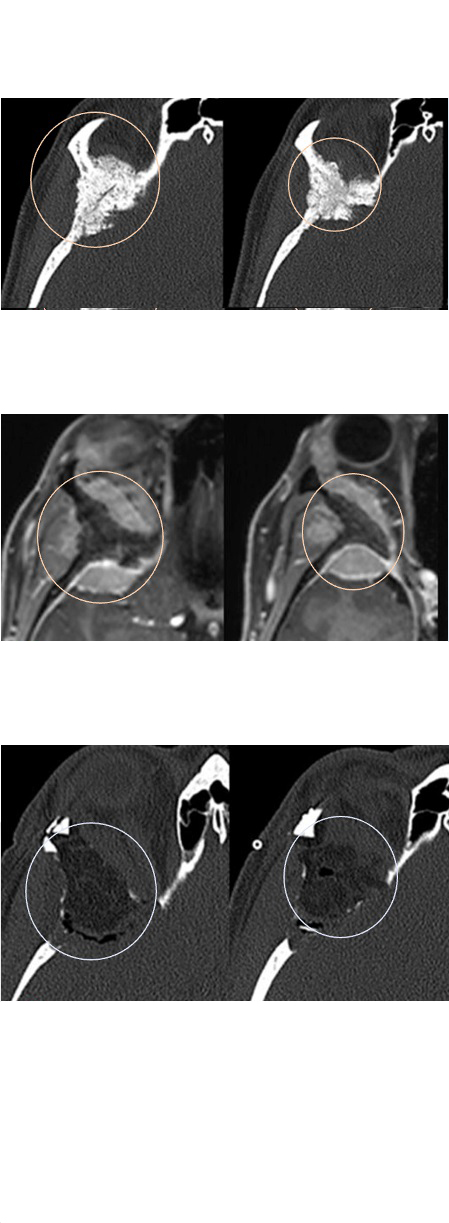

一名38岁女子出现了轻微的眼球突出。CT和MRI核磁共振显示轴外的骨质增生肿瘤,怀疑是蝶眶脑膜瘤(图1A和B),选择保守观察。一年后,肿瘤增长,眼眶周围疼痛和眼球突出恶化。没有孕激素摄入史,眼科检查正常。

患者术后恢复良好,没有术后并发症。CT和MRI证实完全切除肿瘤(图1C)。术后6天拆线,患者在的状态下出院,几乎没有可见的疤痕,眼球突出治愈(图2B)。